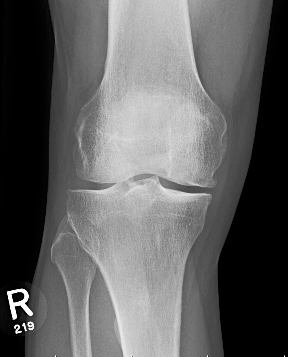

Young varus with OA Failed medial OCD with varus